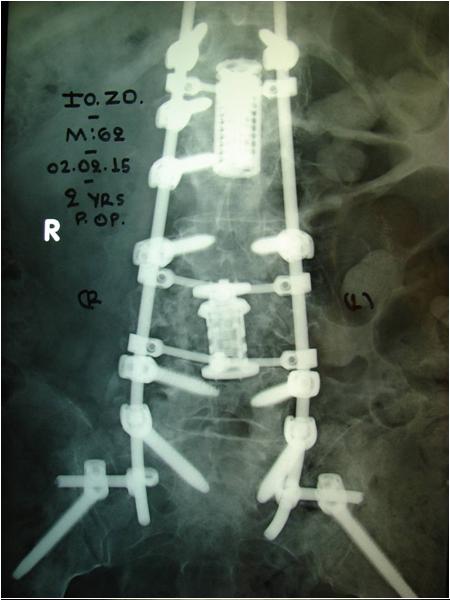

Εικόνα 6: Μετεγχειρητικές ακτινογραφίες μετά την τελευταία χειρουργική επέμβαση (α.β) και δύο έτη αργότερα (γ,δ)

Παρατηρείται η καλή στήριξη της σπονδυλικής στήλης και η διατήρησή της.